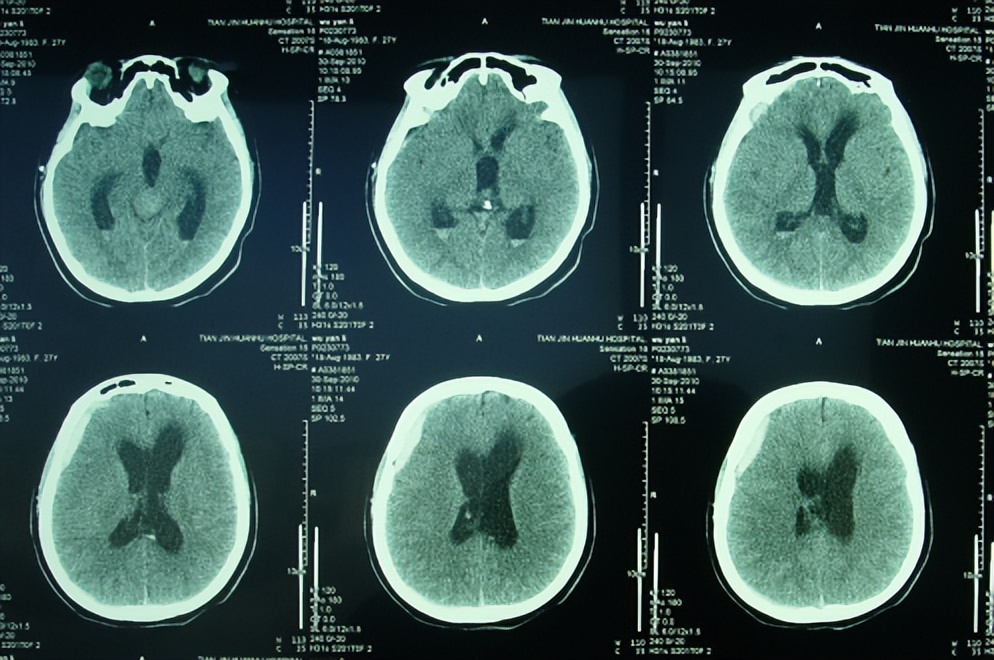

脑积水分流感染性致肢体震颤芭蕾舞足脑室镜第三脑室造瘘术和6次脑室

23个月女孩 第三脑室大 看ct和核磁单

月13日(脑室镜第三脑室造瘘术后58天),脑ct显示的脑室再次扩大(图-13)

三脑室层面 三脑室上层面

病例学习:第三脑室脉络丛乳头状瘤一例

石记莲,女性,54岁,头痛,头晕8月,加重伴行路不稳5月,三脑室肿瘤,脑膜

第一周,轴位和矢状位平扫 ct 显示第三脑室顶有一圆形结节;侧脑室

2.1日发病时ct,鞍上池及三脑室可见高密度影